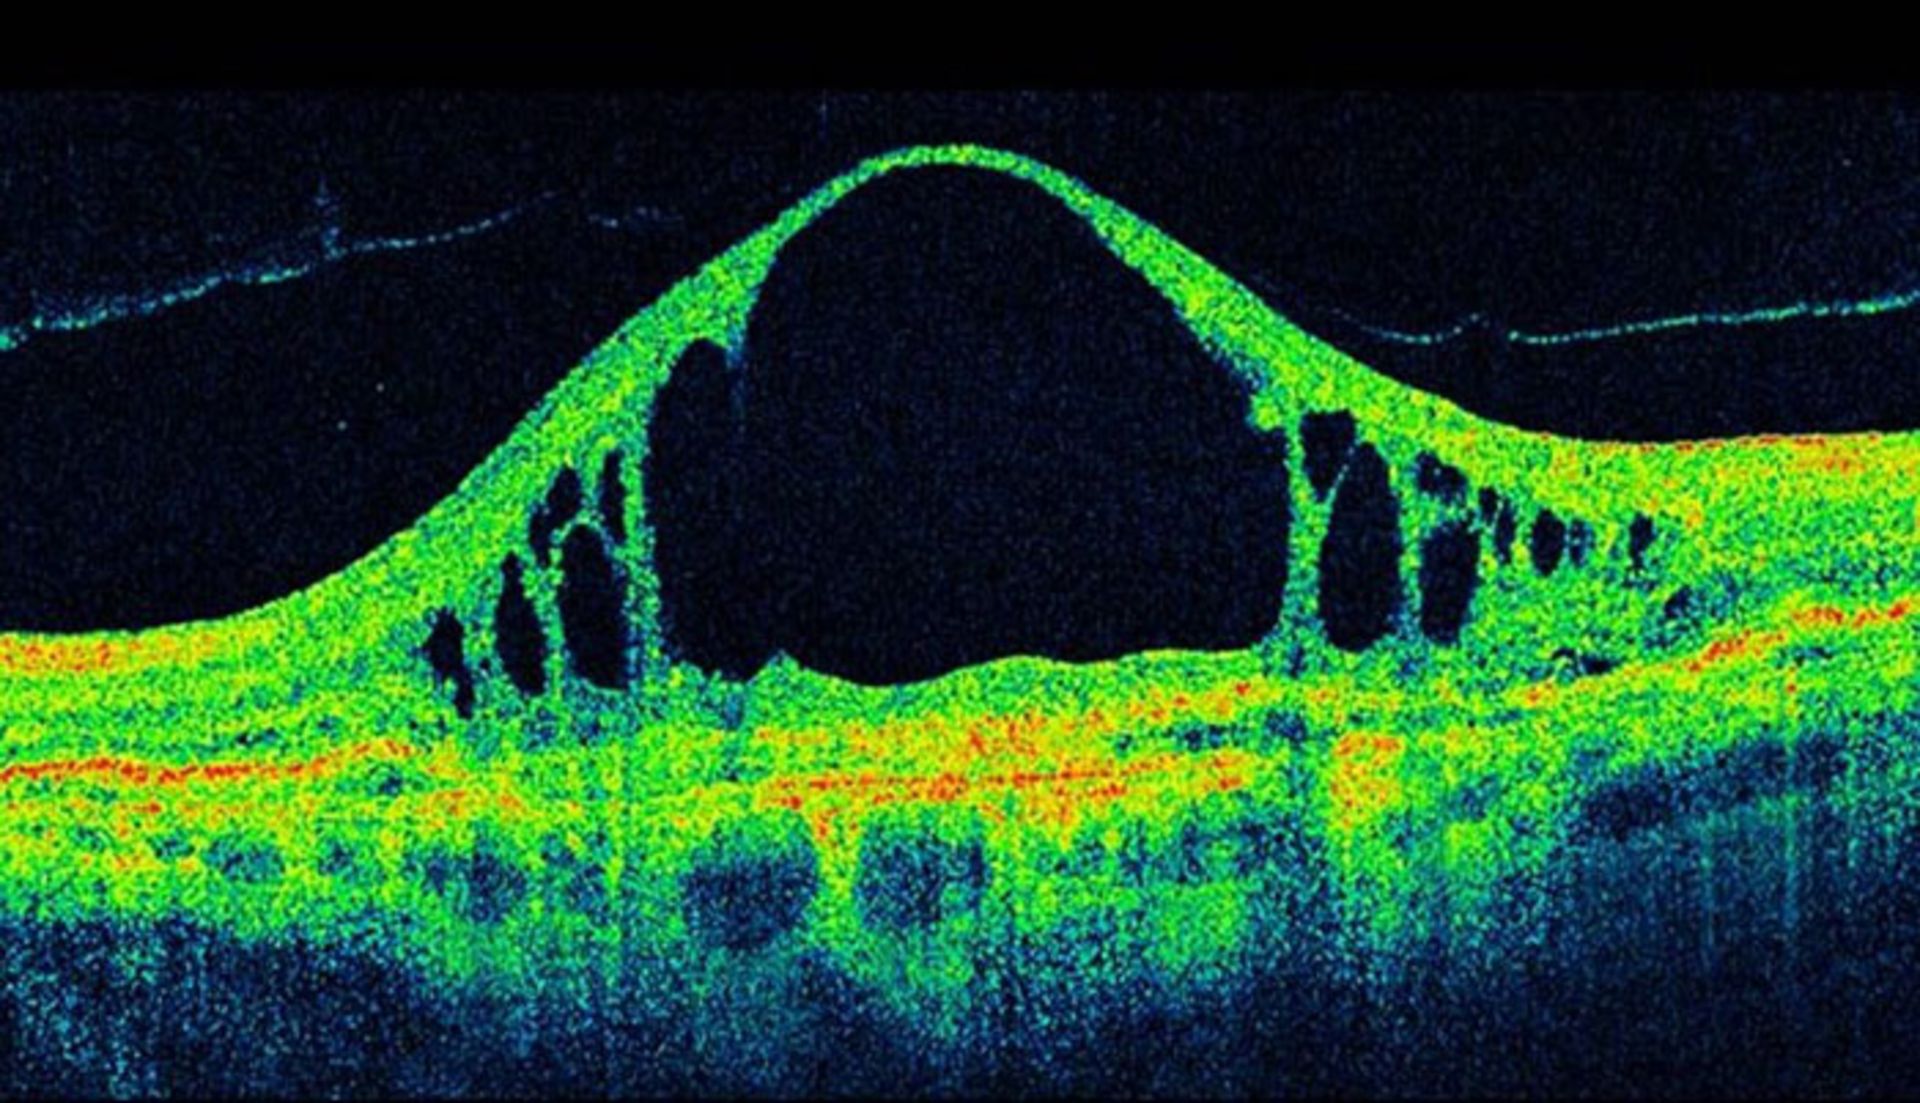

این نرم‌افزار که جزئیات آن در ژورنال علمی Nature Medicine منتشر شده، بر اساس سیستم یادگیری عمیق طراحی شده و از الگوریتم‌های خاص برای تشخیص الگوهای مشابه در داده استفاده می‌کند. در این مورد، داده همان اسکن سه‌بعدی چشم بیمار است که با تکنیک مقطع‌نگاری همدوسی اپتیکی یا OCT انجام می‌شود. تولید این اسکن‌ها حدود ۱۰ دقیقه زمان می‌برد. در خلال این فرآیند نور نزدیک به فروسرخ به سطح چشم تابانده می‌شود. سپس یک تصویر سه‌بعدی از بافت چشم ایجاد می‌شود. این فرآیند برای تشخیص سلامت چشم، فرآیندی مرسوم است. در واقع اسکن‌های OCT ابزارهای پزشکی حیاتی هستند؛ چرا که تشخیص زودهنگام بیماری چشمی عموما بینایی بیمار را حفظ می‌کند.

اسکن oct